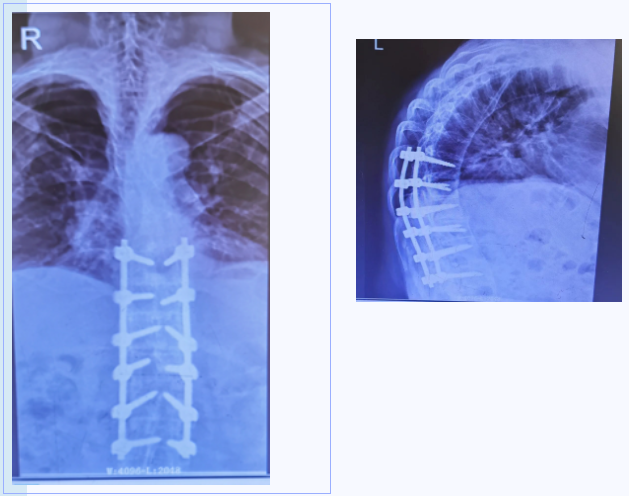

术中唤醒患者实验双下肢感觉运动,与术前无异,治疗过程中没有出现加重脊髓损伤情况。随着手术顺利结束,团队心里悬着的石头悄然落地,手术室同事报以微笑鼓励,逐渐缓和的紧张气氛中,殊不知大家已与死神完成一场“生死决斗”,推拉揪扯间,成功为患者实施T12/L1骨折脱位切开复位、椎管减压、椎间盘切除、椎间植骨融合钉棒系统内固定术。

(患者骨折脱位复位固定良好)